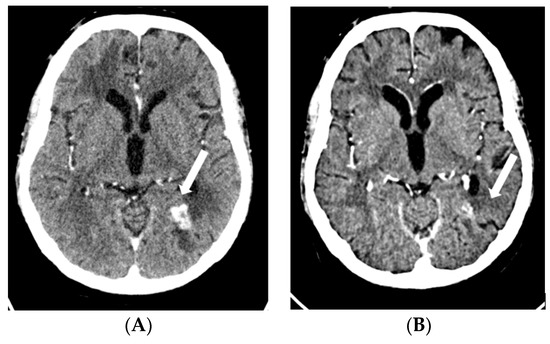

2.1. Case 1

2.2. Case 2

2.3. Case 3